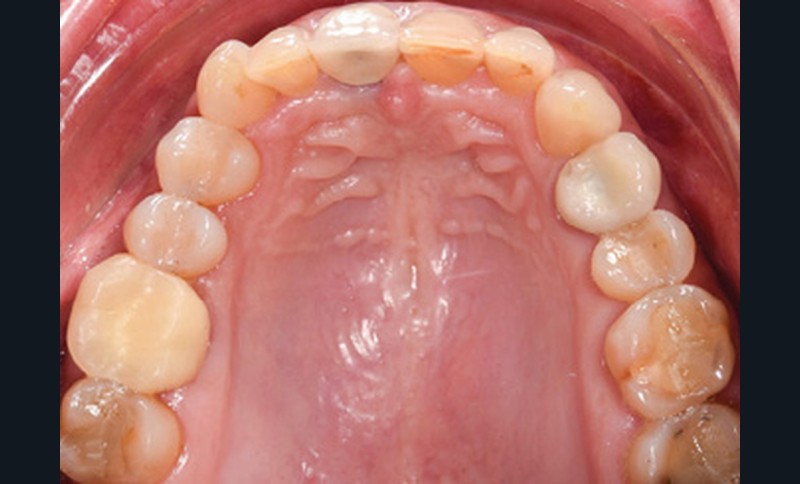

Examen endobuccal (fig. 2a-e)

L’arcade maxillaire est asymétrique et parabolique. Elle présente une mésio-position du secteur 1. On note des rotations mésio-vestibulaire de 13 et disto-vestibulaire de 23 et une palato-version incisive. Les restaurations prothétiques sur 11, 16 et 24 semblent à refaire. L’arcade mandibulaire est asymétrique et parabolique avec une couronne sur implant en 36.

Dans la dimension transversale, on constate une endoalvéolie maxillaire. Dans la dimension sagittale, on observe une classe II plus importante à droite où elle est complète de 5 mm. Le surplomb est absent et la supraclusion totale (6 mm) par supra-alvéolie mandibulaire.